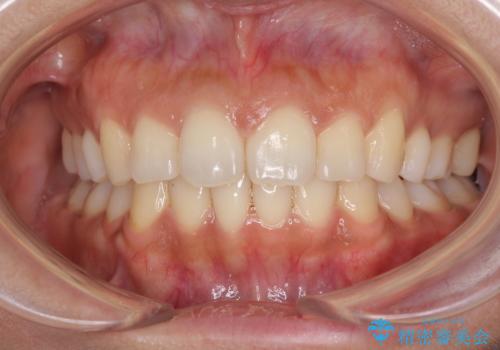

抜歯矯正の後戻り インビザラインによる再矯正治療

- 以前矯正治療をされていましたが、後戻りが起きたことを気にして来院された患者様です。

全顎的に認められた叢生を改善するため、インビザラインにて治療を行うこととしました。

前歯の叢生の改善を目的として、IPR(歯と歯の間を削る)と歯列全体の後方移動によって歯並びを整えることとしました。

臼歯部も含め、叢生が綺麗に改善され、患者様には大変満足していただきました。